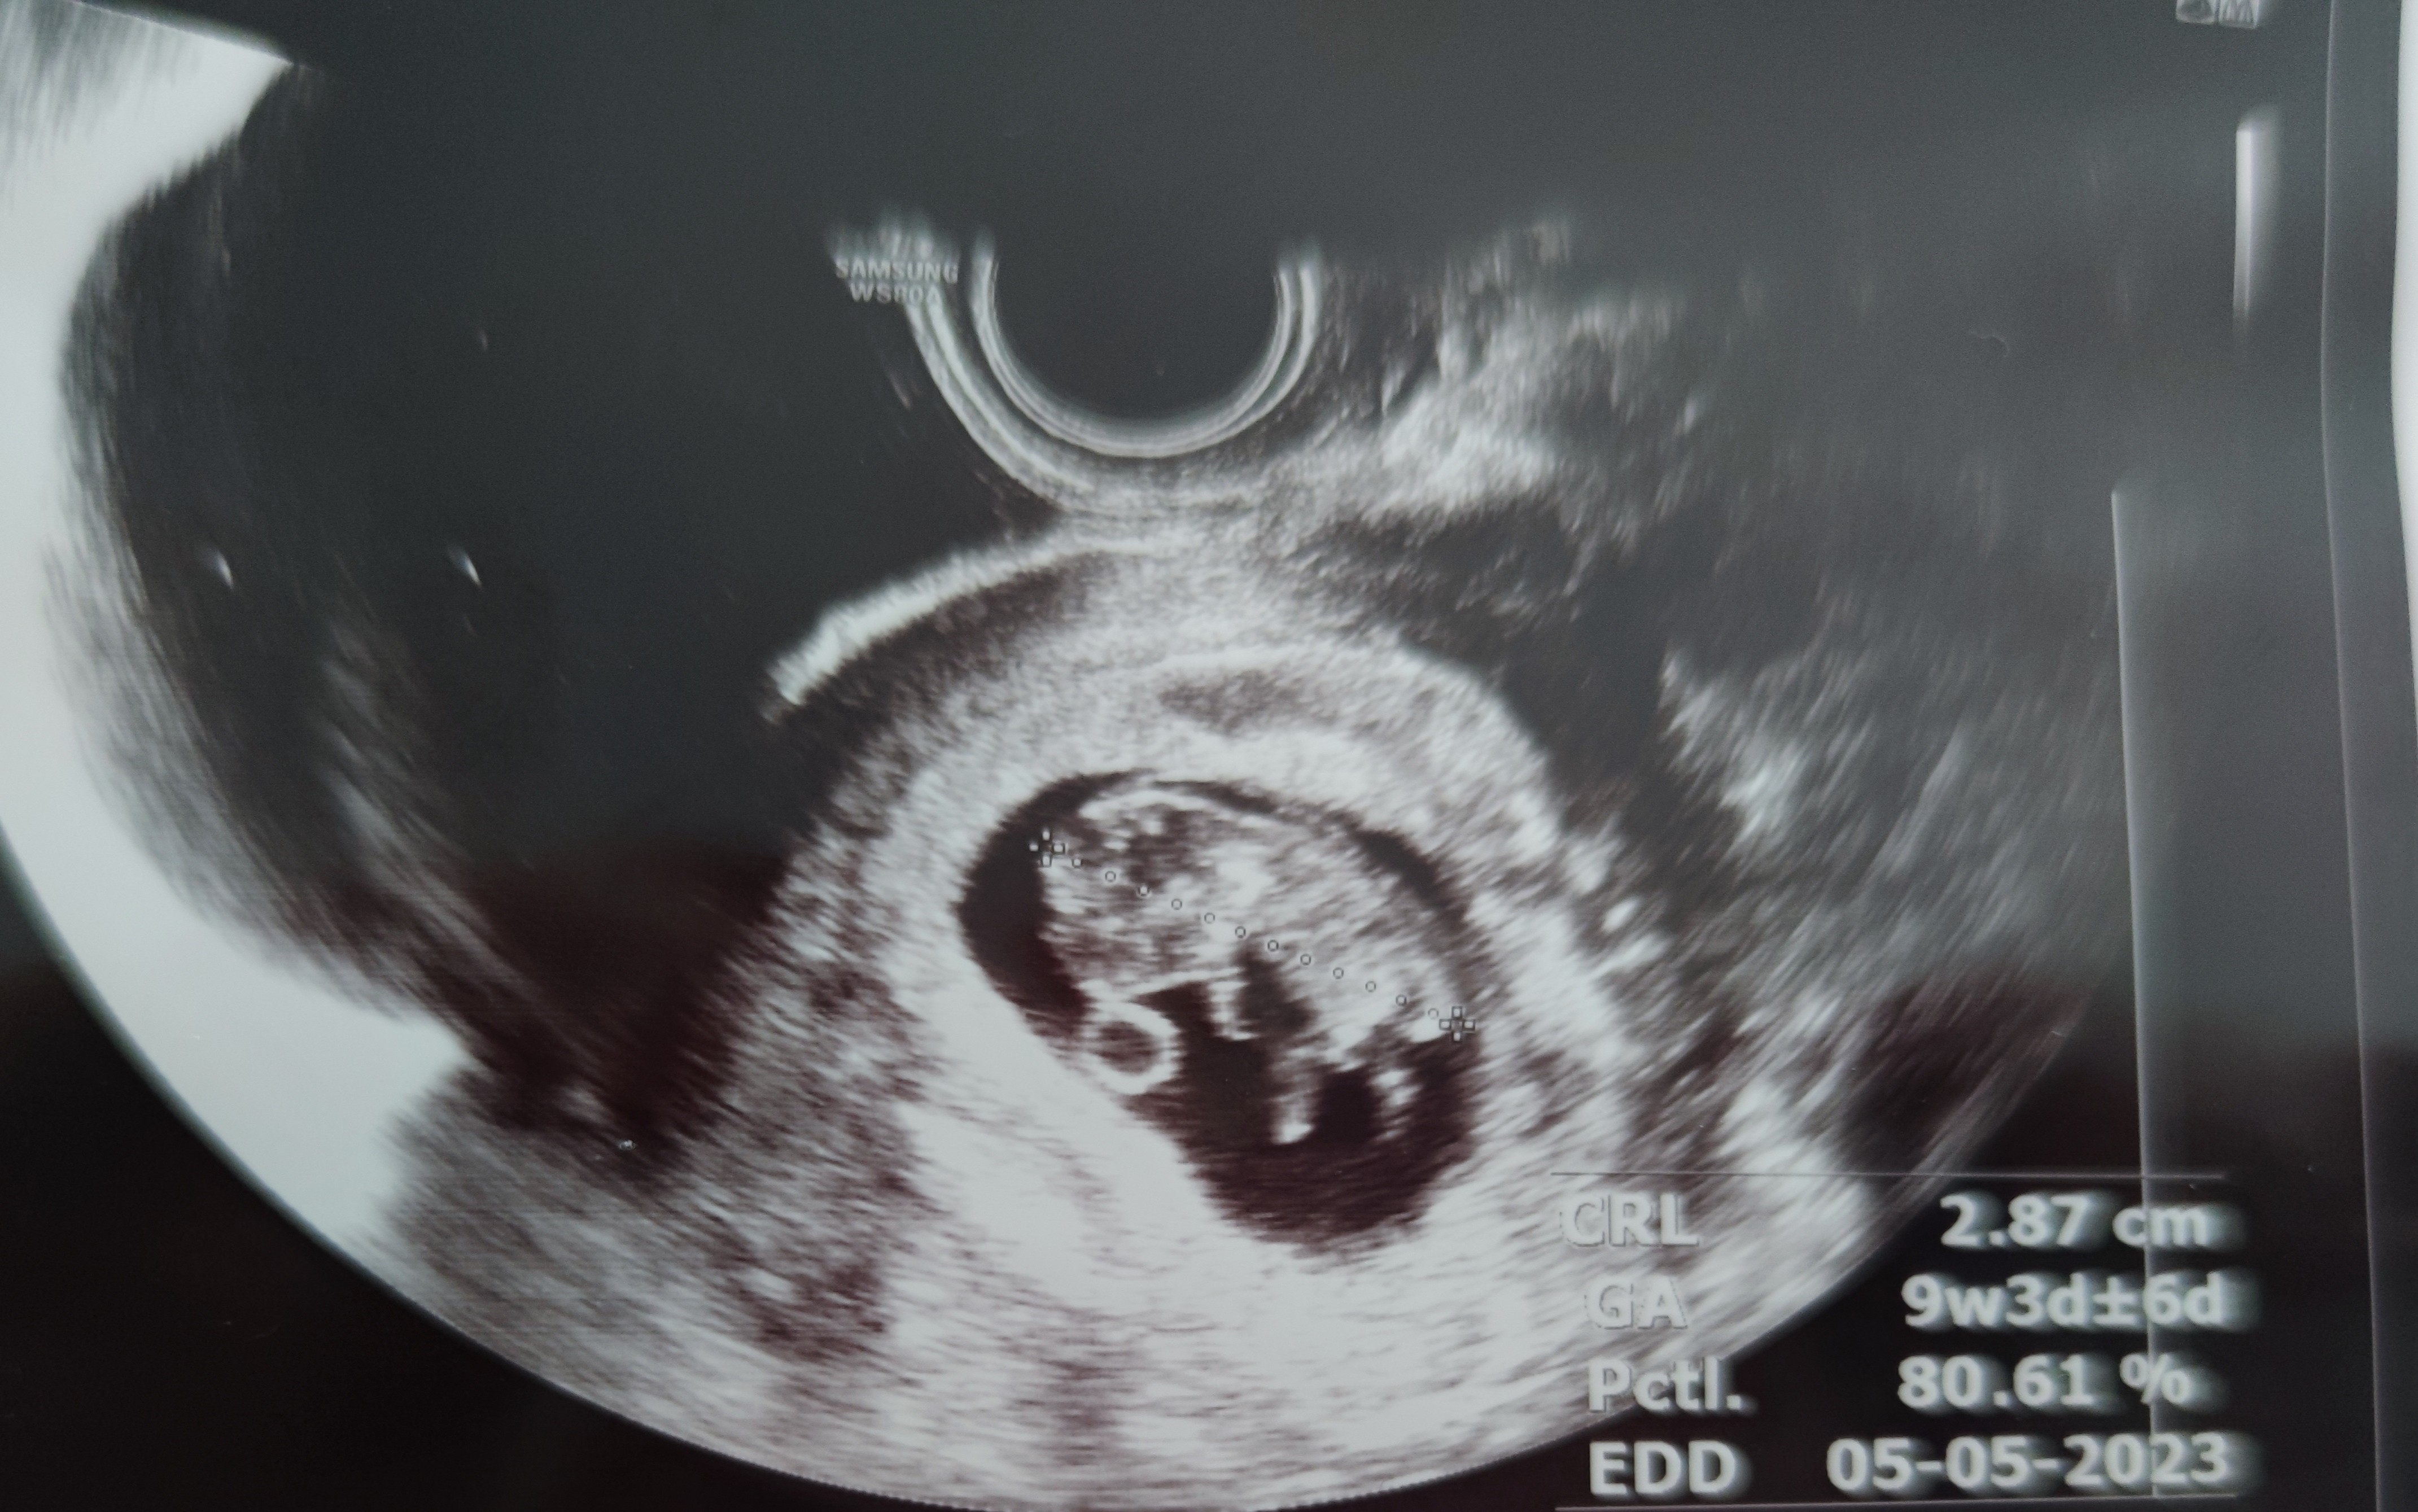

Hej :) dzidzia już prawie 3cm 😍

Mniej się udzielam bo chyba nie do końca chce się przywiązywać do bobasa po pierwszym poronieniu parę miesięcy temu, ale wszystko wskazuje na to że ma się dobrze ;) rusza się, serce biło tylko na obrazie, dźwięku jeszcze nie włączaliśmy ;) dostałam skierowanie na krew i w końcu na kolejnej wizycie założymy kartę ciąży.